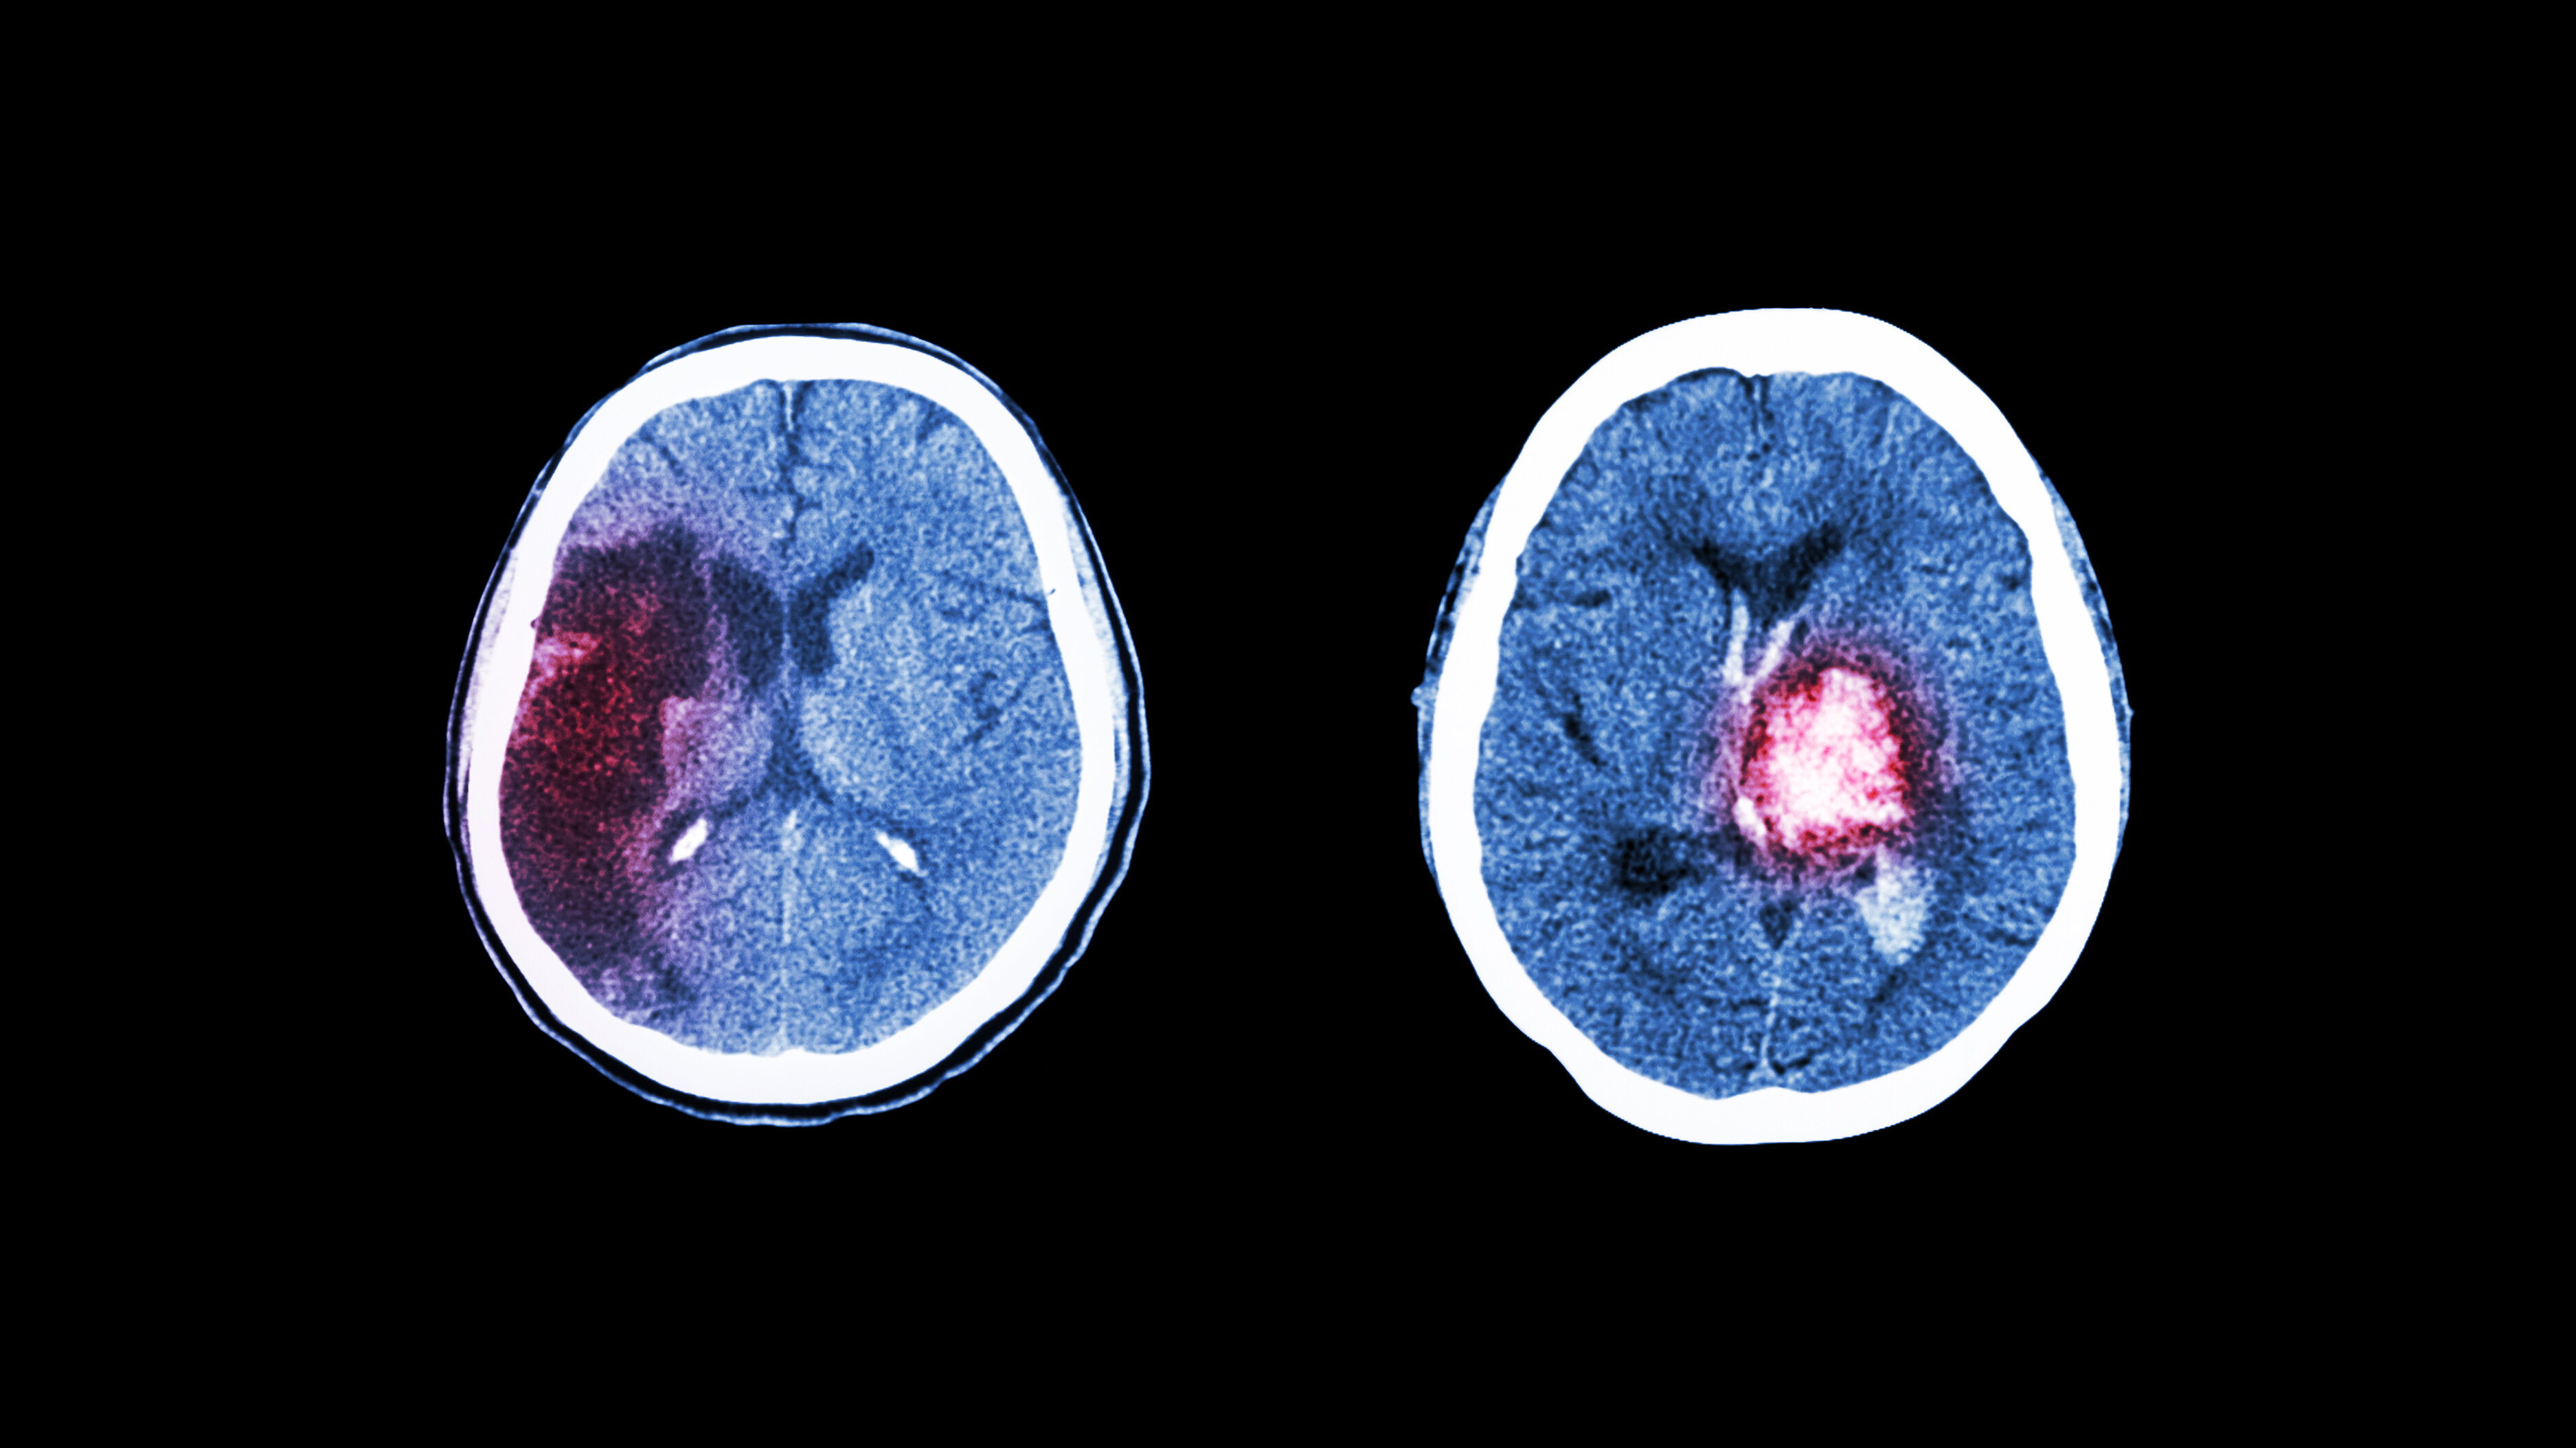

Hvert år rammes cirka 15 000 personer av hjerneslag i Norge (1). Fatigue forekommer ofte som en subjektivt opplevd tilstand etter hjerneslag ledsaget av sterkt redusert energikapasitet, kalt post-stroke fatigue (PSF) (2, 3). I den norske befolkningen opplever rundt 10 prosent utmattelse eller fatigue (4), men forekomsten av fatigue etter hjerneslag er høyere (3).

Hjerneslag er den hyppigste årsaken til funksjonsnedsettelse hos eldre, men adekvat og tidlig rehabilitering styrker mulighetene til å gjenvinne funksjoner i dagliglivet (1). Mange pasienter opplever stor fremgang ved målrettet rehabilitering, men studier viser at PSF kan vedvare i flere år (5, 6). Studier har også vist at PSF kan oppstå på ulike tidspunkter i forløpet etter et hjerneslag (7).

I 91 prosent av tilfellene var blodpropp årsaken til hjerneslaget, mens 9 prosent skyldtes hjerneblødning. Totalt var medianskåren for hjerneslagets alvorlighetsgrad på NIHSS 3, og interkvartilbredden gikk fra 1–6. Kun 19,3 prosent rapporterte ingen tidligere sykdommer. Det var 22,4 prosent som rapporterte om depresjon 4–6 uker etter hjerneslaget. Deltakerne rapporterte at de i utstrakt grad mottok rehabiliteringstjenester 4–6 uker etter hjerneslaget. Kun 34,3 prosent rapporterte at de ikke mottok noen form for rehabiliteringstjenester (tabell 2).